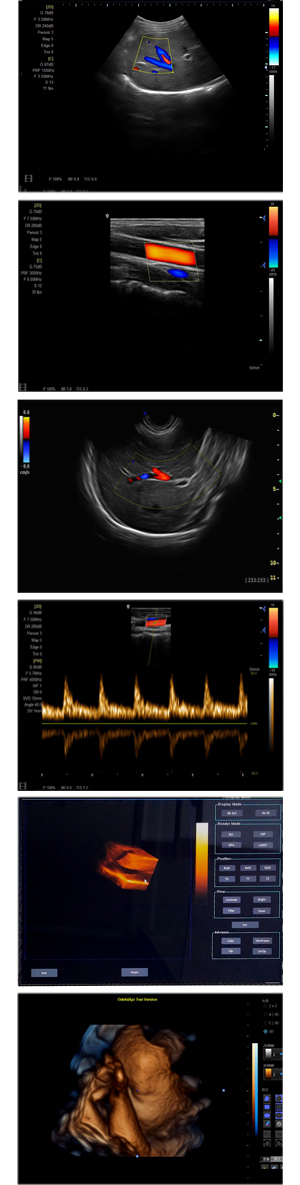

XF-7500型,秉承先鋒彩超技術(shù)之精華,擁有高雅大氣的獨特外型,為最新一代應(yīng)用型數(shù)字彩色多普勒診斷系統(tǒng),魅力與實力相融合。可廣泛適用于腹部、婦產(chǎn)科、心臟、小器官、乳腺、肌骨及外周血管等諸多方面的診查,讓您在臨床超聲診斷應(yīng)用領(lǐng)域得心應(yīng)手,綻放異彩!

突破的成像技術(shù)

● 3D/ 4D成像技術(shù)/選配

● 應(yīng)用于腹部、腎臟、泌尿系統(tǒng)、產(chǎn)科、婦科、盆腔、大動脈、肌肉組織、小器官、乳腺、心臟等

● 能量多普勒成像(PDI)

● 彩色血流量圖(CDE)

● 脈沖頻譜多普勒成像(PW)

● 組織諧波成像技術(shù)

● 全數(shù)字波束形成技術(shù)

● 聲速優(yōu)化成像技術(shù)

● 彩色血流分辨增強技術(shù)

● 自適應(yīng)斑點噪聲抑制技術(shù)